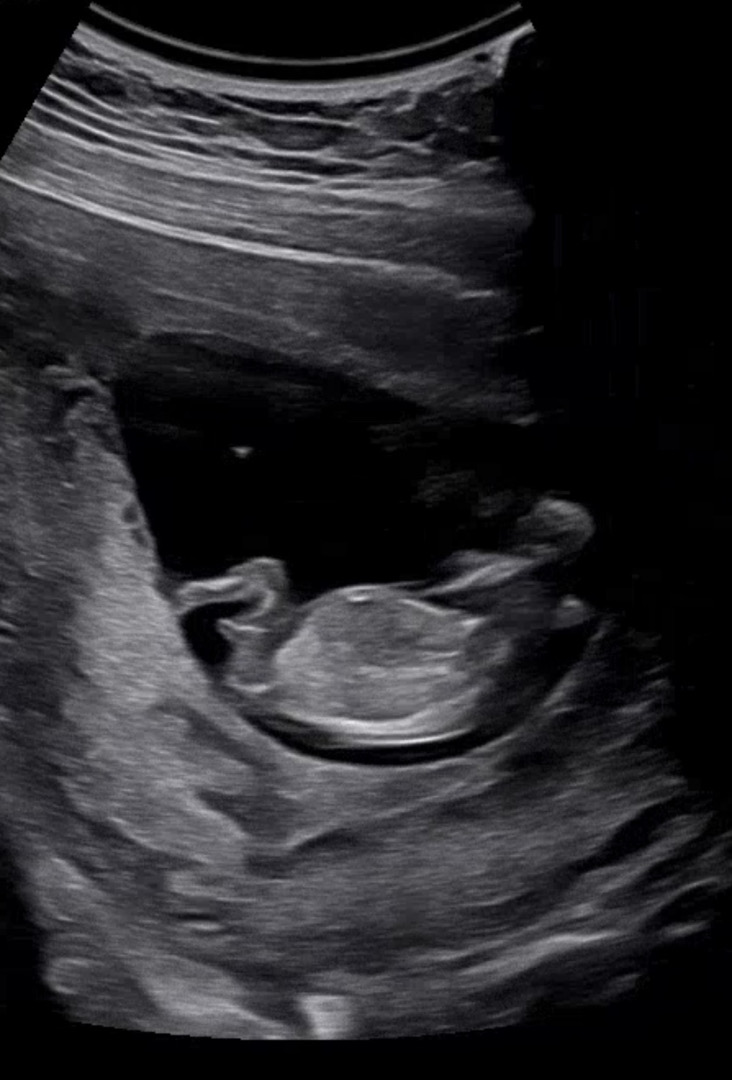

11주 6일차 각도법

아들인지 딸인지 궁금하네요ㅎㅎ!! 각도법으로 성별 알 수 있을까요~??👶🏻